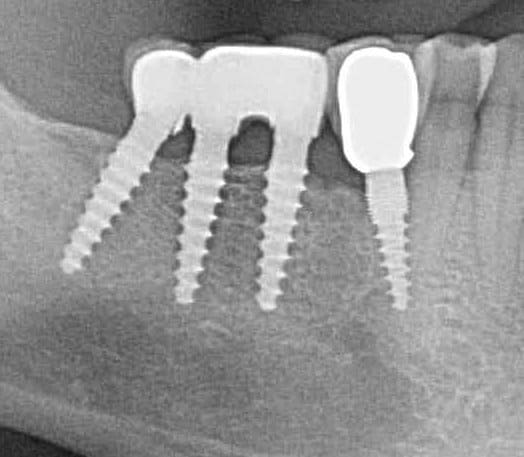

pour répondre à ta question : depuis 1994 , oui d ailleurs dans un des cas présentés tu as une radio après 10 ans :-)! (46 47 )

Exp dans ce cas 4,5/10mm en 36 dans un site d'extraction récent placé en 12mm soit deux millimètres plus profondément j'ai scellé un prep cap angulé 5 degrés niveau 1/0 dont la limite s'arrête à la rainure de la tête carrée, pour 37 3,5/10mm placé en 10mm j'ai utilisé un prep cap 2/2mm. On prend vite l'habitude moi j'utilise que 2 modèles en zircone et 3 en titane..